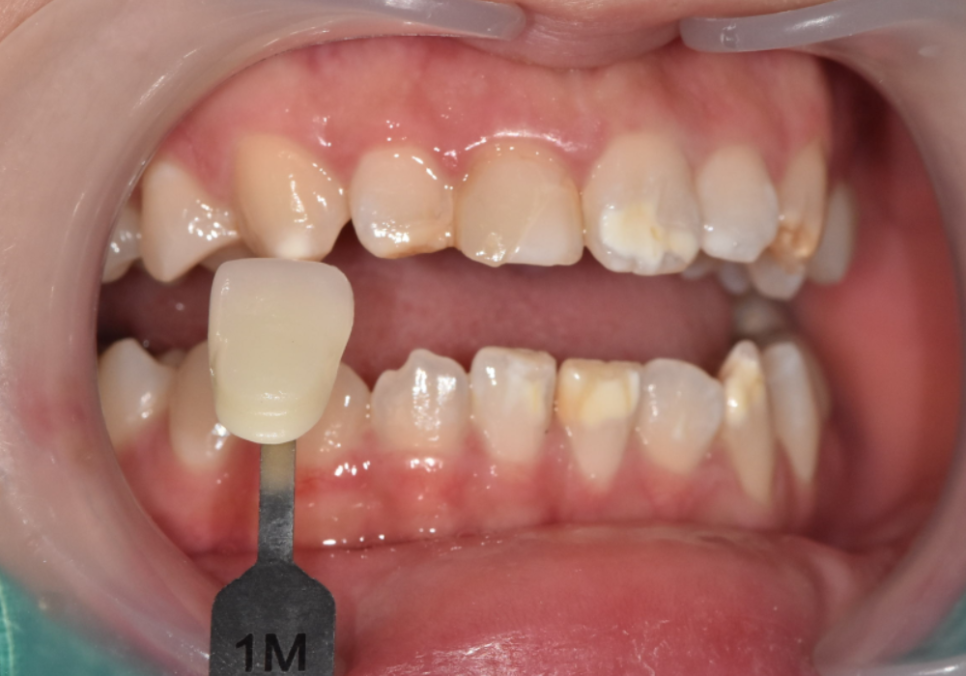

그래서

힘을 상대적으로 덜 받는

앞니는 라미네이트,

씹는 힘이 집중되는

송곳니 부위는

강도가 쎈 지르코니아 크라운으로

치료 방법을 나누어 선택했습니다.

서로 다른 치료를 적용했지만,

색상과 형태는

주변 치아와 자연스럽게 어울리도록

세밀하게 조율했습니다.

이 과정에서는

원내 기공소에서 기공사와 직접 소통하며

보철 제작을 진행했기 때문에,

미세한 색감이나 형태 조정도

즉각적으로 반영할 수 있었습니다.